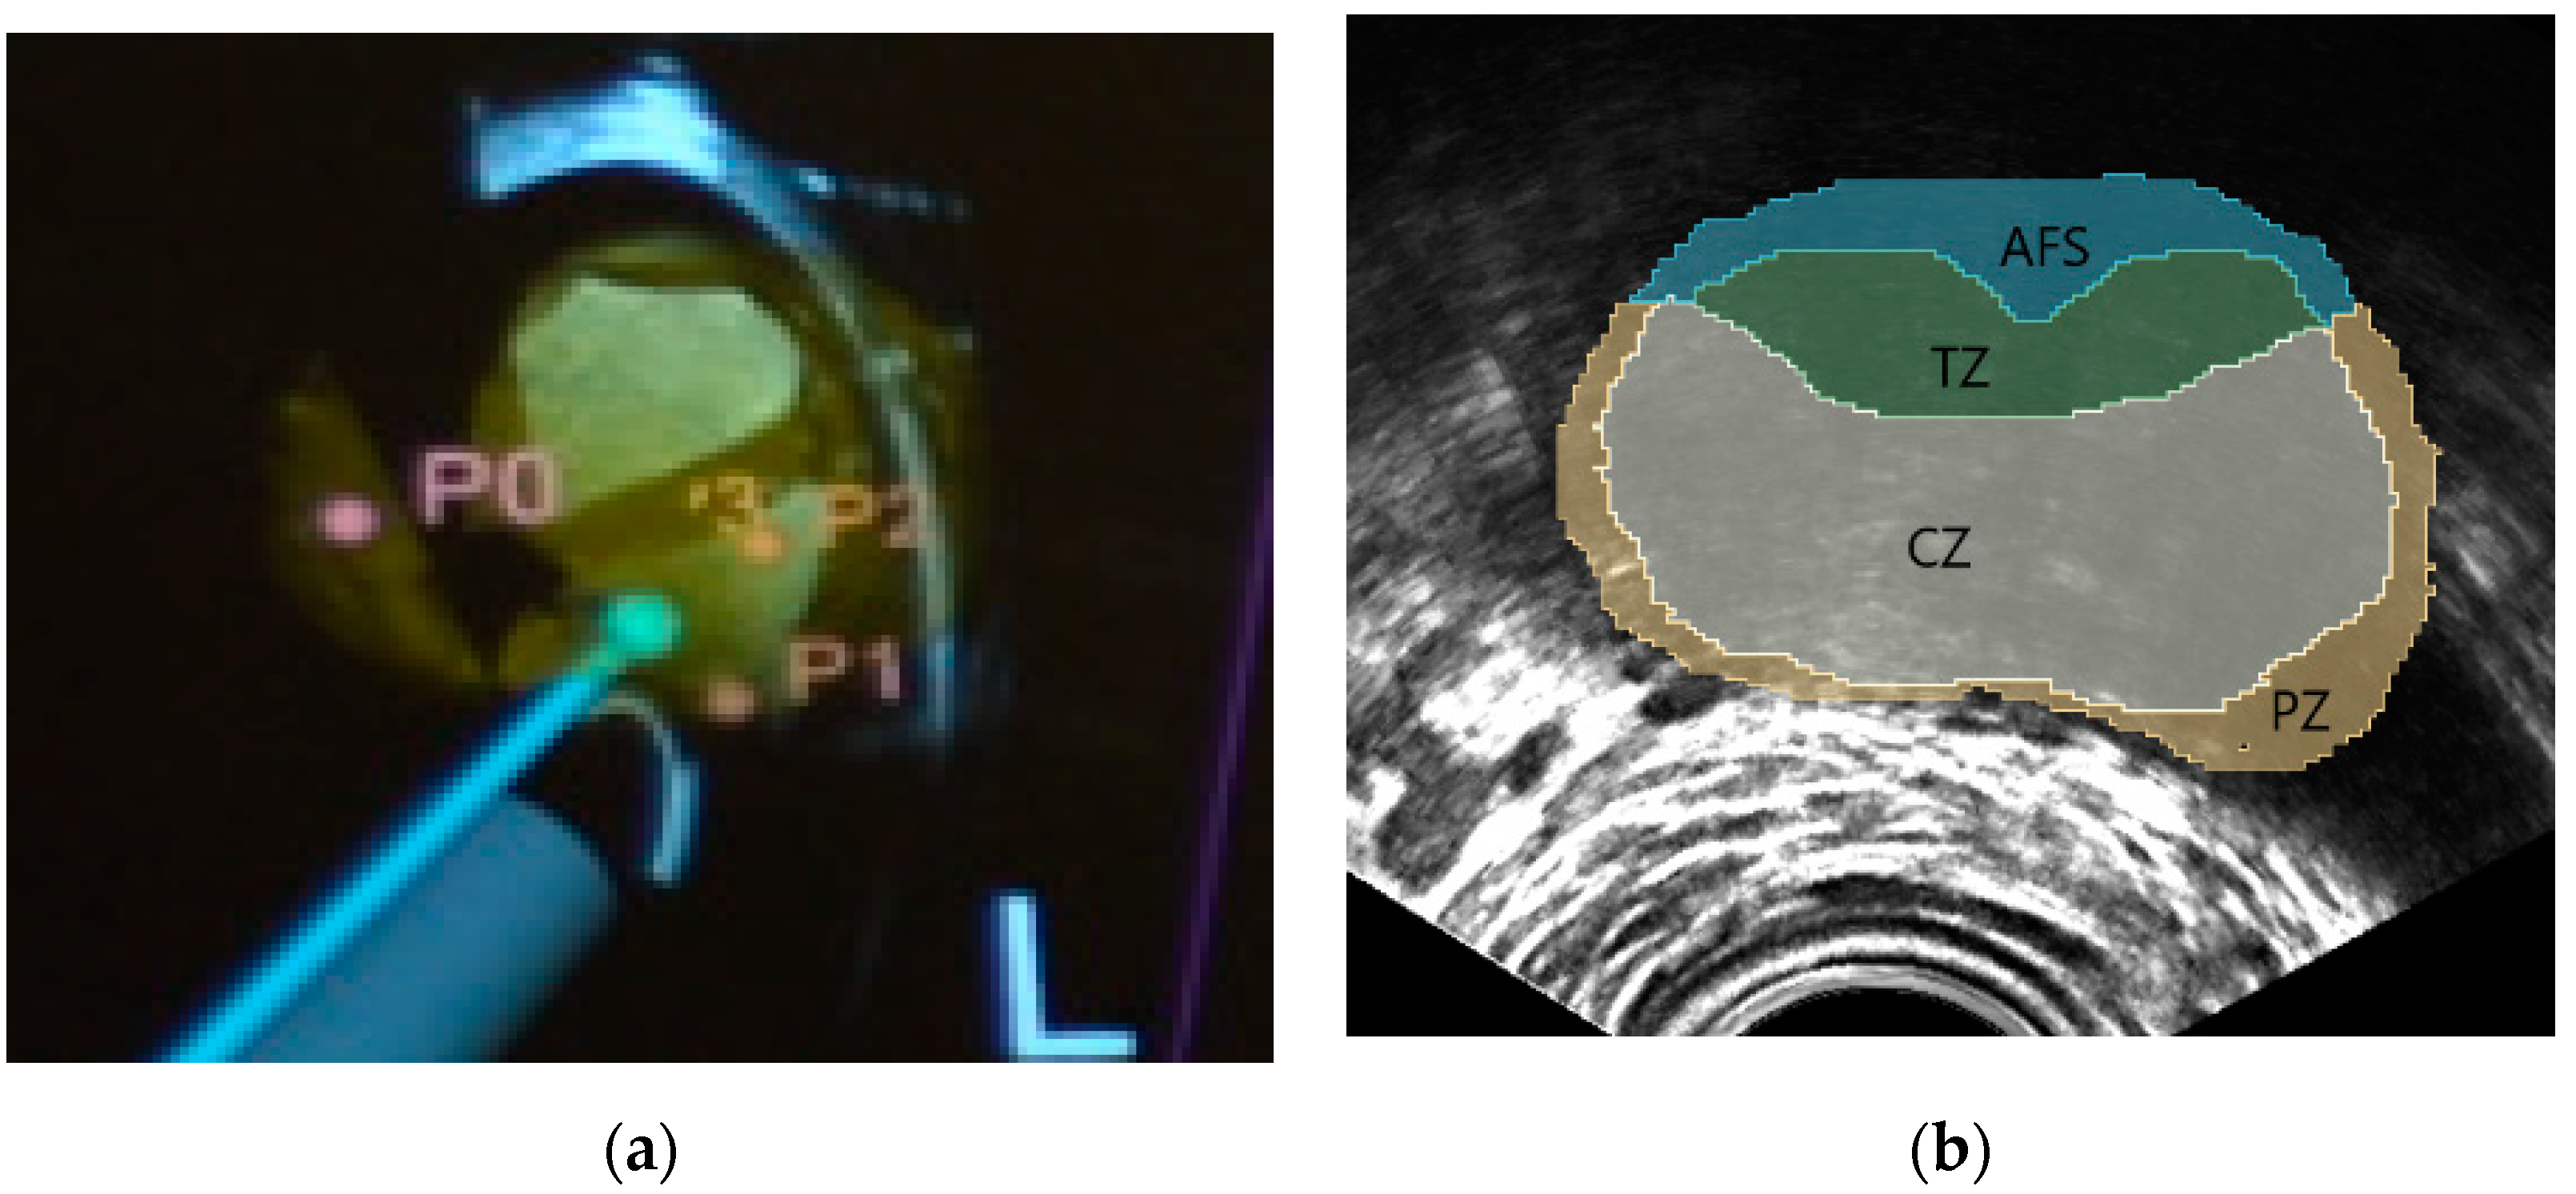

NaviPBx guides the physician with real-time “labels” painted over the live 2D TRUS image, such as in Figure 4a, showing models of the TRUS transducer (grey), biopsy needle (magenta), prostate gland (yellow) and biopsy target locations (pink), that are overlaid on the live 2D TRUS image. The physician interfaces with NaviPBx through a lightweight user interface optimized to execute only the necessary workflow while hiding all other functions. The system records all intra-operative data (e.g., time-stamped ultrasound, tracker, video, audio, rendering scenes, user actions, and internal variables) for offline analysis and validation when the user interface is turned back on at full functionality.

Figure 4.

Typical system guidance views of the NaviPBx prostate biopsy system. (a) Models of the TRUS transducer (grey), biopsy needle (magenta), prostate gland (yellow), and the biopsy target locations (pink), that are overlaid on the live 2D TRUS image. (b) McNeal zones painted on the live 2D TRUS image.

Labeling the McNeal zones (central, transition, peripheral and anterior zones) in TRUS is a critical function for planning and sampling the systematic biopsy target locations, typically 12 cores [7]. For this purpose, we plan to reuse our previously developed implementation. Our current prototype starts with a set of anonymized labeled prostate MRI volumes, with segmentations of the prostate and the McNeal zones. Having segmented the prostate in 3D TRUS, we select the MRI scan with the most similar prostate, based on statistical shape analysis, then perform a deformable elastic registration between the prostate glands in the selected MRI and the 3D TRUS, with an existing module (e.g., BRAINSFit) of 3D Slicer. Finally, we apply the resulting deformation field to map the McNeal zones onto the 3D TRUS, and then paint the McNeal zones on the live 2D TRUS image, such as in Figure 4b. In a preliminary experiment with seven expert urologists, this module correctly labeled the McNeal zones 92% of the time, mislabeling only the central zone where very few prostate cancers start [26]. We expect occasional mislabeling to disappear when we use a larger set of model-training MRI volumes, including a pool of patients with advanced disease. Over 80 anonymized labeled MRI/TRUS volume pairs are currently available to us for this purpose, from previous research. It must be noted that the most important aspect is the correct labeling of the McNeal zones, while the metric accuracy required for the zonal contours is quite lenient, considering the smallest size of significant prostate cancer to be biopsied, 0.5 cc in volume [11]. Altogether, this prostate anatomy labeling prototype module promises clinically sufficient performance when fully integrated in NaviPBx.